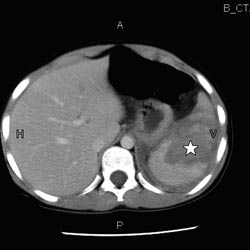

Av de resterende 11 pasientene var ni gutter og to piker. Hyppigste skademekanisme var fall (seks tilfeller), mens sykkelvelt og akeulykker var årsak i to tilfeller hver. Median alder ved innleggelse var åtte år (spredning 1 – 12). Median skadegrad av milt bedømt ved CT var 4 (spredning 3 – 4) (fig 1). En 12 år gammel pike ble hemodynamisk ustabil kort tid etter innkomst. Hun fikk transfusjonsbehandling, men var fortsatt ustabil og gjennomgikk deretter vellykket intervensjonsradiologisk embolisering av miltarterien. De øvrige pasientene var hemodynamisk stabile etter innleggelse. Median liggetid i sykehuset var fem døgn (spredning 3 – 8), hvorav null døgn (spredning 0 – 4) i overvåkningsavdeling. Mediant antall ultralydkontroller som ble utført i etterforløpet av miltskadene, var to (spredning 0 – 4). Resultatet av disse kontrollene viste begynnende eller fullstendig normalisering av milten. Anbefalt redusert aktivitetstid etter skaden var mediant fire uker (spredning 3 – 6), frem til en poliklinisk avsluttende kontroll. Det ble ikke registrert senblødninger eller andre komplikasjoner hos noen av pasientene.

CT vil ofte være den foretrukne modalitet ved primærutredning av stumpt abdominaltraume hos barn. På grunn av strålebelastningen CT-undersøkelsen representerer, bør indikasjonsstillingen være god. Skader av milten bedømmes internasjonalt ved vurdering av CT-bilder og graderes etter stigende alvorlighetsgrad etter den såkalte organ injury scale (6). Hemodynamisk stabile barn med isolert miltskade kan behandles ikke-operativt uavhengig av skadegrad bedømt radiologisk (1) – (4). I vårt materiale hadde vi kun alvorlige skader (grad 3 og 4) (fig 1), men ikke-operativ behandling lot seg likevel gjennomføre hos alle pasienter.